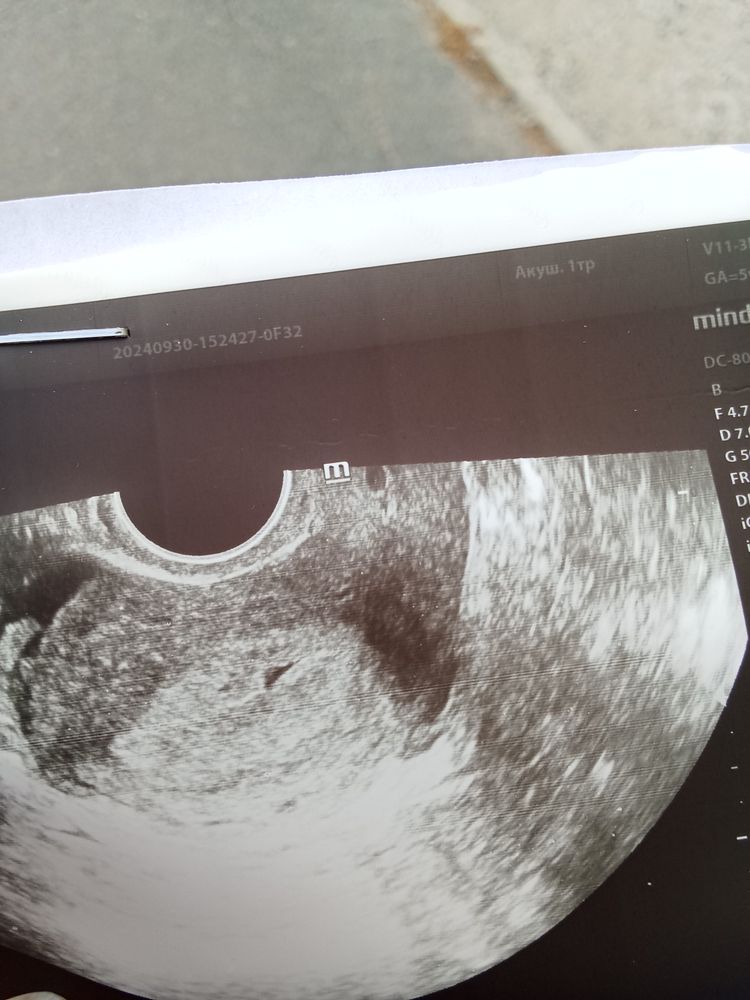

Olly, ХГЧ 94, другая лаборатория правда. Вечером похоже ХГЧ скаканул. Фрау верх до сдачи крови, нижний вечер

Olly, у меня при бхб было 30;29;36 и упало. Я немного просто переживаю что бы не ВБ. А с остальным справимся. Я записалась на УЗИ сегодня, понимаю, что ничего не найдем определенного, но хоть какой то шанс исключить ВБ бы мне. А так только ждать. Вообще изначально рост не ахти. Я примерно знаю как рос до 14 дпо, судя по тестам. На 10 дпо- 2-3 ед, не больше. На 12 дпо 10-15. На 14-32; 16-49, 18- 94, но другая лаборатория. И после сдачи крови вечером тесты ярче стали. Завтра сдам, на 20 дпо и уже что то думать. Я на хороший вариант уже не рассчитываю. Только б не ВБ🤞🤞🤞. Я антибиотики пила вплоть до 12 ДПО, отменить нельзя никак было, вырвала зуб мудрости,пошло осложнение и с 9 или 8 дпо тонзиллит гнойный. Не везёт моей крошке.